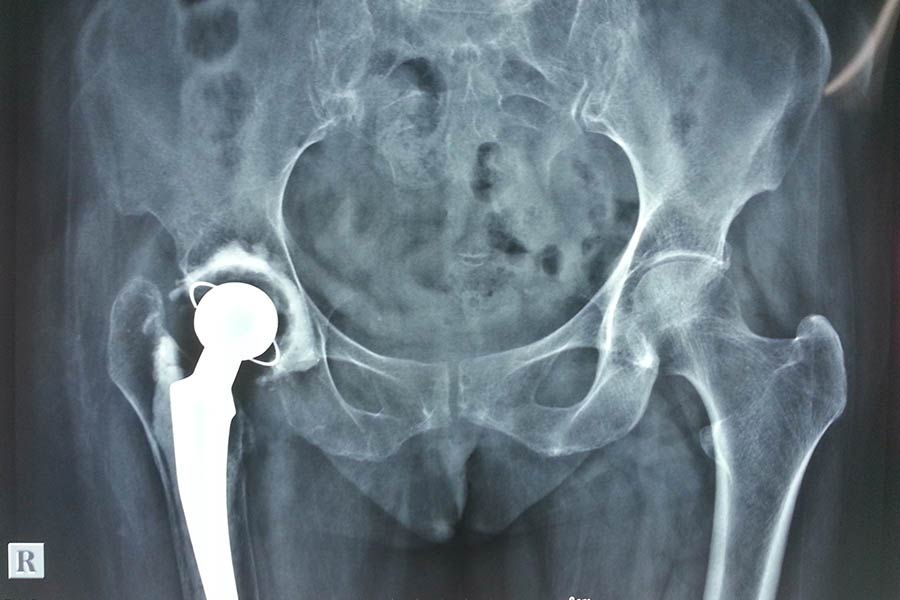

Total Hip Replacement

Case 1